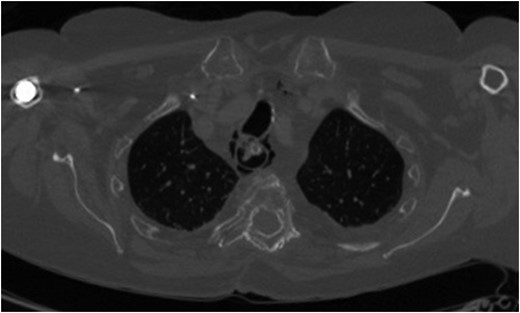

For management of this oesophageal perforation and definitive management of her gastric perforation, the patient was referred to the authors’ unit, a tertiary referral centre for upper GI surgery. In the first instance, a water-soluble contrast swallow was performed to assess the status of the oesophageal perforation. This demonstrated no leak of contrast (Fig. 3) and therefore a diagnostic endoscopy under general anaesthesia was performed in order to assess the cervical oesophagus and also the known gastric perforation. This endoscopy demonstrated a healed oesophageal perforation but persistent gastric perforation with established cavity (Fig. 4) containing an existing transabdominal Robinson drain. The cavity was felt to be of a size likely to heal without the need for further negative pressure vacuum therapy, so a T-tube was placed across it. The established track of the existing abdominal drain was used to guide placement of the T-tube. A nasojejunal feeding tube was placed under vision.

Water-soluble contrast swallow study demonstrating free flow of contrast from oropharynx to stomach with no evidence of leak.